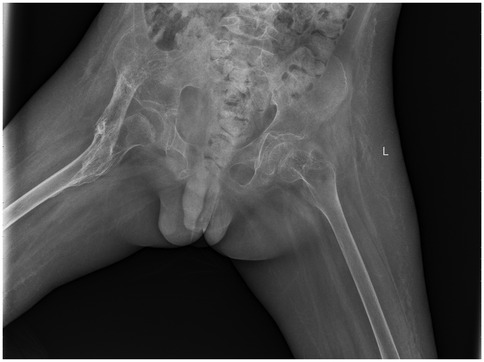

By April 2021, repeat radiographs showed a well-demarcated, band-like high-density ossification consistent with the anatomical course of the iliopsoas muscle, the cortical shell is ≥1 mm and continuous (Figure 2). The mass extended across the hip joint and partially encased it. After excluding surgical contraindications, surgical excision was performed under general anesthesia. The child is in the supine position; a 12 cm L-shaped anterior incision was made over the right hip. After incising the skin, careful blunt dissection was performed; the soft tissues were used to retract the femoral nerve and artery medially, exposing the HO. The HO was separated proximally to the anterior superior iliac spine and distally to the area above the lesser trochanter. The mass was transected at both ends using surgical instruments, and the surrounding soft tissues were carefully detached. The ossified segment was successfully excised. Bone rongeurs were used to smooth the bony edges. Intraoperative assessment revealed that hip flexion reached 90°. Fluoroscopy confirmed complete removal of the HO. Bone wax was applied to control bleeding, and the incision was closed in layers. The amount of bleeding was about 350 ml, and red blood cells were transfused to replenish blood volume. A negative pressure drainage tube was left in place after the operation and was removed after 48 h when no obvious drainage fluid was found.

Figure 2

X-ray of the pelvic region showing the pelvis, hip joints, and upper femurs. The image is labeled with \

Figure 2. 2021.04. A strip-like high-density ossification shadow is consistent with the long axis of the iliopsoas muscle, with clear edges, growing across the joint and surrounding the joint.